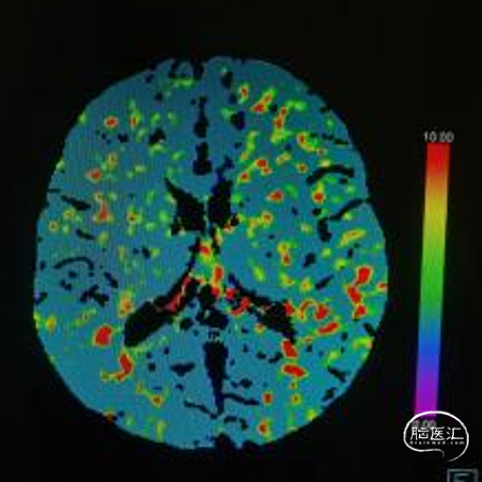

➢术前CTP

MTT